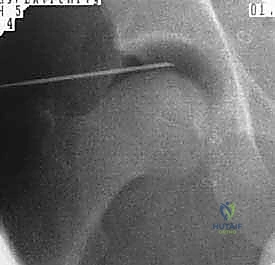

يتم غالباً استخدام التخدير العام أو النصفي. يوضع المريض على طاولة عمليات خاصة تُسمى (Traction Table). يتم سحب الساق برفق شديد لفتح مسافة صغيرة جداً في مفصل الورك (حوالي 1 سم) تسمح بإدخال الكاميرا والأدوات الجراحية بأمان دون إتلاف الغضروف.

2. إحداث الشقوق وإدخال الكاميرا

يتم عمل شقين أو ثلاثة شقوق صغيرة. يُضخ سائل معقم داخل المفصل لتوسيعه وغسل أي بقايا، ثم يتم إدخال كاميرا الألياف الضوئية (Arthroscopy) التي تنقل صورة مكبرة وعالية الدقة (4K) إلى شاشات العرض.